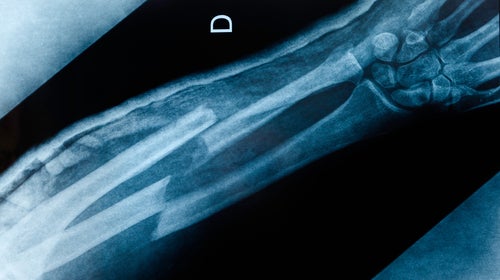

An x-ray image of an boken arm with double fracture: radius and ulna. (Photo: Getty/iStock)

I was climbing near Taos, New Mexico, and fell more than 20 feet into some boulders because of a belaying accident. My left hand hit first and was nearly snapped off at the wrist. It took several surgeries to reattach it, followed by two years of rehab.